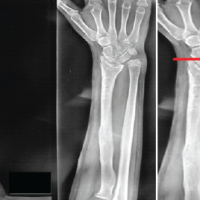

She was initially investigated with plain radiographs and this did not show any obvious pathology. Therefore, further investigation with MRI magnetic resonance imaging was requested of the left shoulder. . The MRI scan showed signal changes within the deltoid muscle consistent with diffuse oedema on the proton density weighted sequence and there was no evidence of plexiform neurofibroma (Fig. 1).

She underwent nerve conduction and electromyography studies and the results were within normal limits in particular excluded an axillary nerve lesion, with axillary nerve M-wave apmplitude of 14.1 and terminal latency of 3.3 with normal motor action potentials seen within the deltoid. This confirmed the absence of an axillary nerve lesion. There was an intitialinitial elevation in erythrocyte sedimentation rateESR (26 – 73 mm/h) and C reactive proteinCRP of 12;, however, they returned to normal parameters when her symptoms abated. . The patient was screened thoroughly to rule out connective tissue disorders with antinuclear, antineutrophil cytoplasmic antibodies,ANCA and extractable nuclear antigen (ENA) antibody panels, as well as diabetes. . Blood investigations for creatine kinase and lactate dehydrogenase levels taken during the acute phase were within limits. . A sequential MRI scan was performed upon resolution of symptoms showing a reduction in the observed level of oedema within the deltoid (Figure Fig. 2). ). A specialist opinion form the neuromuscular unit was obtained and they confirmed that the appearances are consistent with focal myositis in the deltoid.